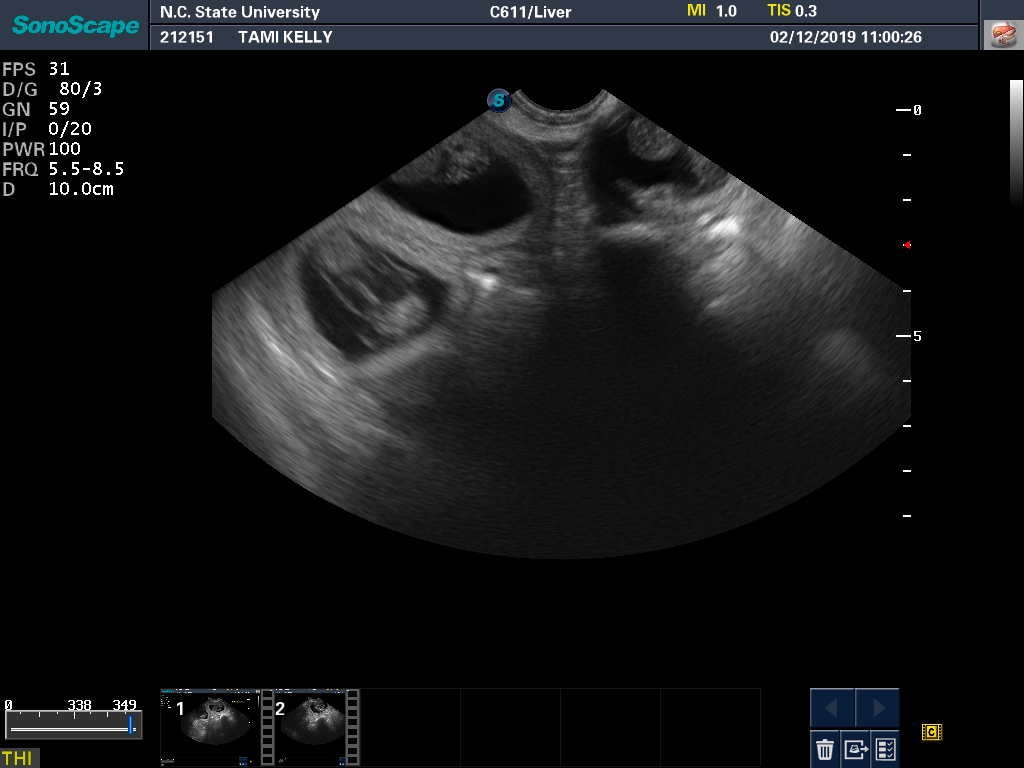

12 Feb

Tami had another ultrasound and progesterone check. All looks well. Here is a a good view of one of the puppies from the ultrasound monitor. And a view showing that there really are three puppies.